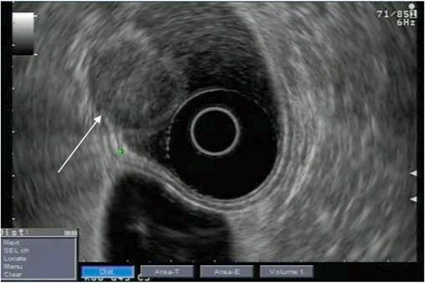

Det första instrumentet tillverkades 1980 och bestod av en enkel mekanisk ultraljudstransduktor kopplad till ett vanligt gastroskop. I dag finns två typer av elektroniska ekoendoskop: det radiella och det linjära. Det radiella instrumentet återger en ultraljudsbild i 360° som är vinkelrät mot instrumentet, medan det linjära instrumentet ger en bild som är parallell med instrumentets axel. Bara det linjära instrumentet möjliggör vägledning av en nål för finnålsaspiration, biopsi eller injektion genom att nålen kan följas i realtid vid införandet i vävnaderna (Figur 1).